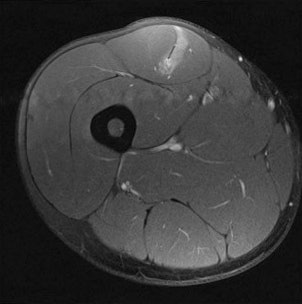

In many cases, MRI scans can identify muscle injuries, but radiologists want to be able to provide an indication of the severity of the injury so the referring clinician can decide how long the athlete needs to refrain from sport to ensure satisfactory healing. Evidence about their ability to provide this information is mixed, according to James.

Between 2002 and 2016, the features of muscle injury that confer a poor prognosis were explored in multiple studies. James explained aspects of injury that must be taken into account with this assessment, including length of lesion, extensive edema on MRI, tendon involvement, and higher cross-sectional involvement -- all of which are considered to indicate a more significant injury and imply a slower return to play.

Most recently in 2014, a new grading system known as the British athletics muscle injury classification was introduced. This uses some current evidence based on tendon involvement, longitudinal length of injury, and cross-sectional area to propose another system to classify muscle injury. Injuries are graded 0 to 4 based on MRI features. The grades 0 to 4 have an additional suffix of a, b, or c if the injury is myofascial, musculo-tendinous, or intratendinous. This system is routinely used by a small but growing number of clinicians.